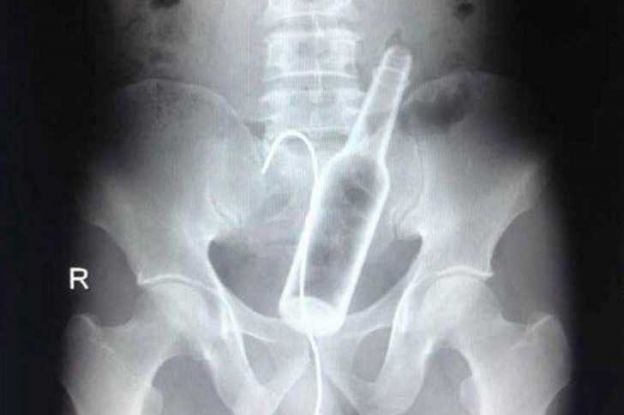

Os objetos mais BIZARROS encontrados no ânus pelos médicos

Garrafa de cerveja